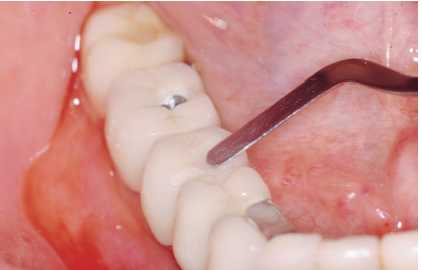

— Eliminación de placa bacteriana y/o cálculo

con curetas de plástico, oro, titanio o carbono composite

(Figura 3), puntas de ultrasonido de carbono composite (Figura

4). No se debe emplear ningún instrumento con punta

metálica, ya que se corre el riesgo de arañar

la superficie del implante y crear nichos en los que proliferen

las bacterias.

Figura 4. Tratectomía con punta de carbonocomposite

Figuras 5a y 5b. Limpieza de cálculo infragingival y

pulido con pasta de baja agresividad